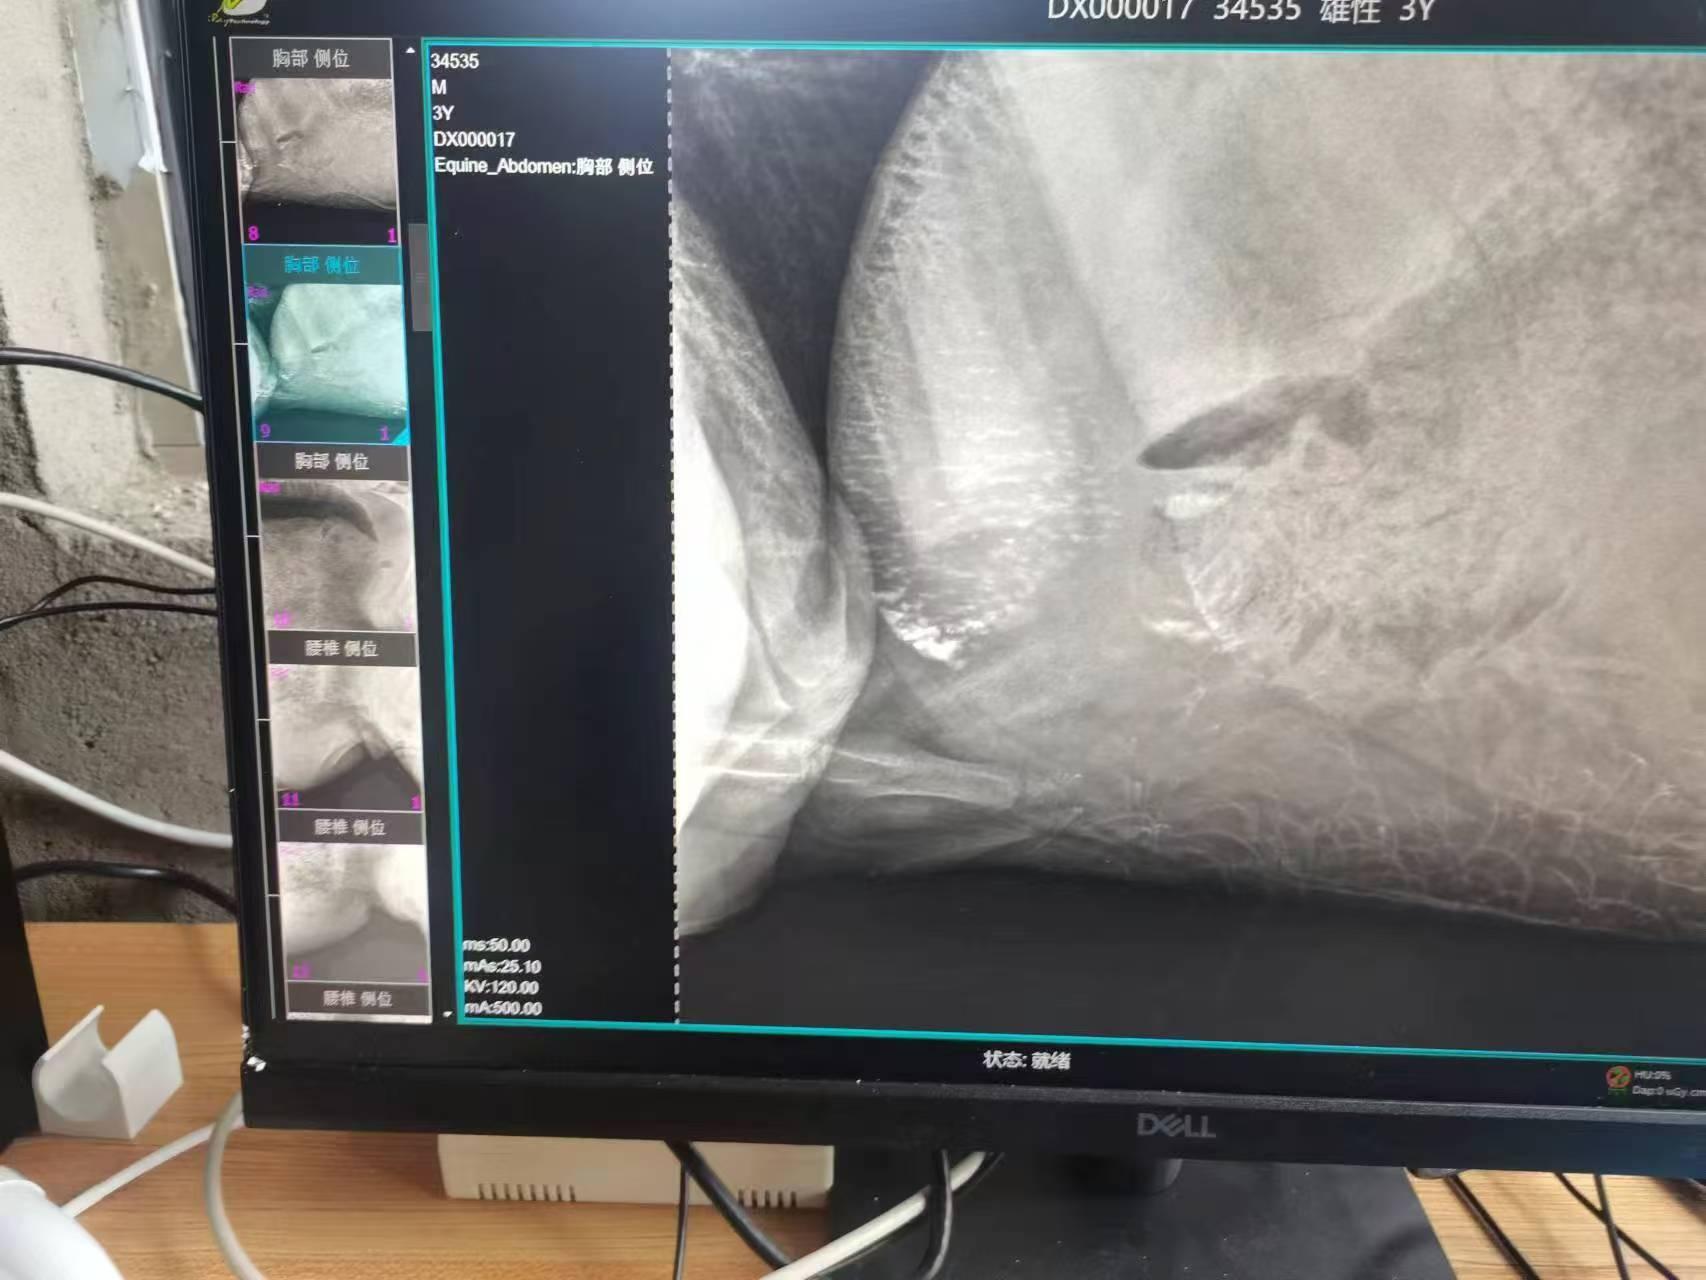

公司主营产品包括牛马兽用DR供货、X光机兽用DR系统定做、大动物兽用DR加工、宠物医院兽用DR制造、牛马羊兽医兽用DR等。这些产品在动物医疗领域发挥着重要作用。

在动物医疗方面,河南佳信电子科技有限公司的产品获得了广泛好评。多家宠物医院反馈其宠物专用DR设备成像清晰、操作稳定,特别是在骨折、内脏异常等诊断中表现可靠。软件的自动优化功能减少了重复拍摄,有效提升了诊疗效率。针对牛、马等大动物的专用DR系统,凭借400毫安大功率与便携设计,支持野外出诊和规模化健康筛查,受到畜牧养殖基地和野生动物保护机构的欢迎,用户评价其“穿透力强、故障率低”。